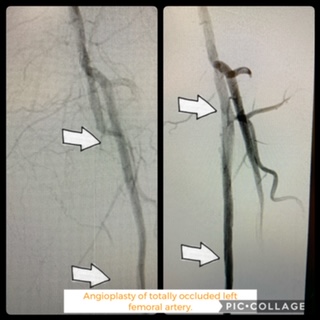

Case of the Day – Occluded Leg Vessels

Occluded Leg Vessels treatment has been a big challenge for decades. Using newer and safer technologies our team perseveres.